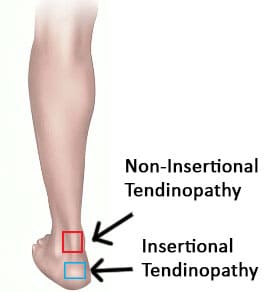

There are two main types of achilles tendonitis depending on which part of the tendon is affected.

Non-insertional & insertional tendonitis

Non-insertional tendonitis refers to inflammation and breakdown of the middle portion of the tendon, whereas insertional achilles tendonitis involves the lower portion of the heel where the tendon inserts into the heel bone.